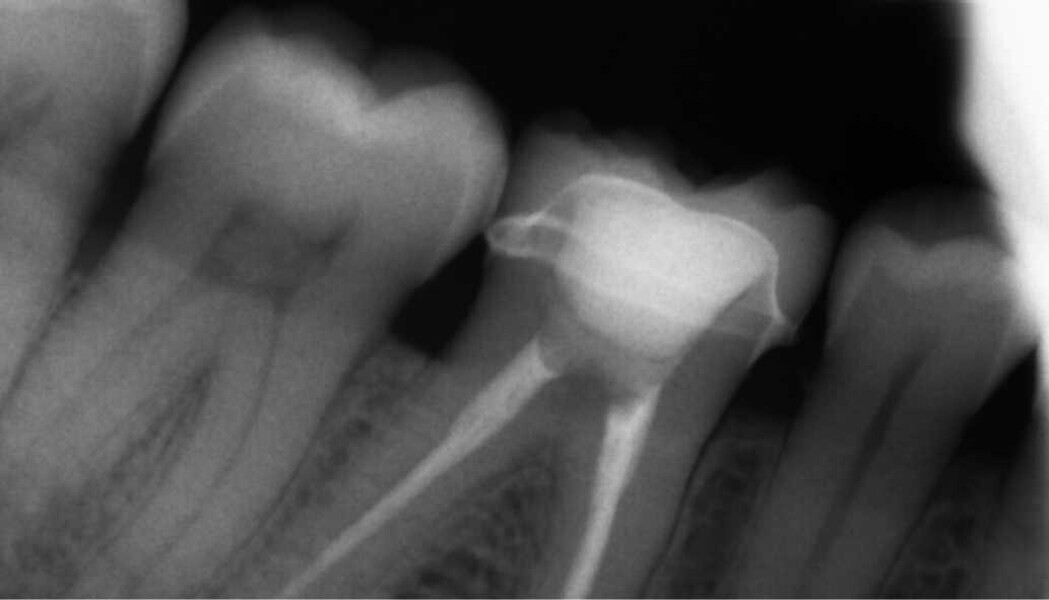

Fig. 2. Situación después de la reconstrucción del muñón con resina (Tetric N-Ceram Bulk Fill) y la preparación del muñón.